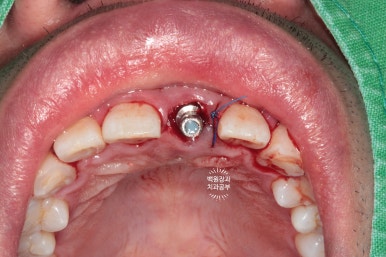

이를 뽑은 자리에 조심스럽게 오스템 BA 임플란트 고정체 (fixture)을 위치시킵니다.

최종 보철물을 만드는데 있어, 주변치아와의 관계를 고려한 임플란트의 위치와 깊이가 가장 중요하기에 많은 경험을 바탕으로 신중하게 해내야해요!!

잘 보시면 발치 즉시 임플란트 시행시 왜 뼈이식을 꼭 해야하는지 알 수있습니다.

지극히 상식적입니다. 제거된 치아 뿌리는 비정형적인 형태를 갖고 있지만, 우리가 사용하는 임플란트는 원기둥 형태이기 때문에 필연적으로 비어있는 공간이 생기기 때문이죠.

이를 발치한 곳 (=발치와)과 임플란트 사이의 공간에

국산 뼈이식 재료를 이용한 뼈이식을 시행하였습니다.

그 gap 부위에 뼈 이식재를 사용하여 꾹꾹 눌러담아 줍니다.

잘 위치된 임플란트 고정체 (fixture)에 임시 지대주를 연결해줍니다.

임시 지대주의 크기는 정해져 있기 때문에, 구강 내 상황은 환자마다 다르므로 그 형태를 다듬어 주어야 합니다.

비유하자면... 키가 작은 사람은 똑같은 기성 청바지를 사도 바지 끝단을 잘라야 하잖아요!!???

임시 지대주의 길이를 짧게 다듬어 아래 앞니에 닿지 않는 것을 확인하고,

그 내부를 임시 재료로 메꿔준 다음에

준비해두었던 임시치아를 연결해주게 됩니다.